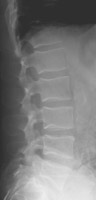

- Click on the image for a larger versionDLateral radiograph of the lumbar spine. Two years prior there was osteopenia, but the fracture was not present.